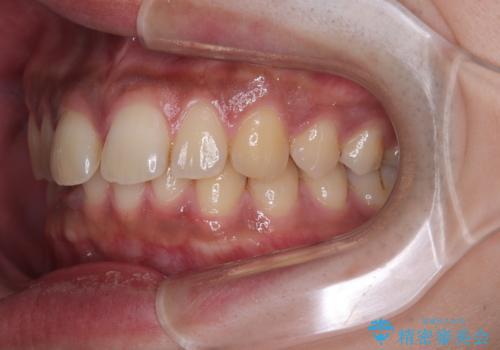

- 上の前歯の正中離開(すきっ歯)と、下顎前歯部の叢生(デコボコ)を主訴に来院された患者様の症例です。

「目立ちにくい装置で治療したい」とのご希望があり、透明のマウスピース矯正であるインビザラインを用いて矯正治療を行いました。

インビザラインは装置が透明で、周囲に気づかれにくいことが大きなメリットです。

取り外しもできるため衛生面でも安心して治療を進めていただけました。